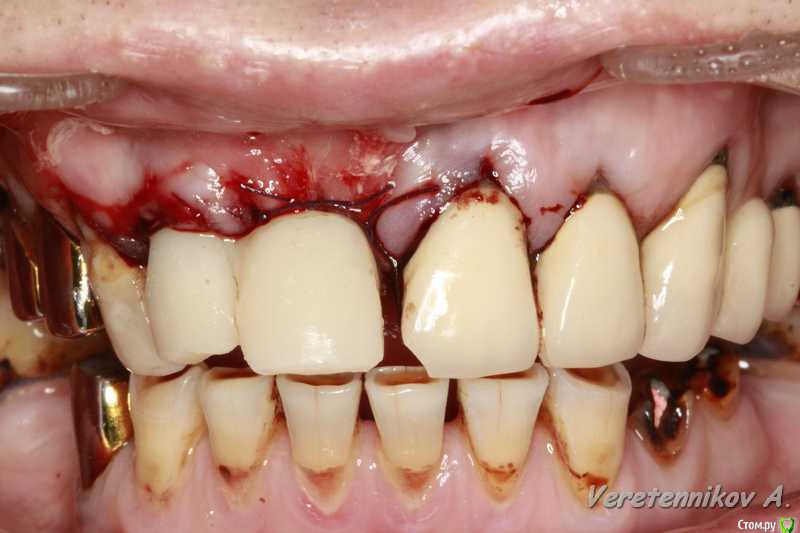

an_ver Опубликовано 26 марта, 2015 Поделиться Опубликовано 26 марта, 2015 (изменено) 11,12..11 трещина корня,вест.часть,12 рыхло все..сгнило.Убрал,кюретаж,11 вест. стенки нет на 2/3.Установил 11-4,2*13;12-3,75*13 мм..все Альфа.Мп3,мембрана эволюшн.11 заглушил,12-временный абатмент,коронка.Шил викрил 4,0. Фсе...пинайте Изменено 26 марта, 2015 пользователем an_ver 7 Ссылка на комментарий

an_ver Опубликовано 27 марта, 2015 Автор Поделиться Опубликовано 27 марта, 2015 Андрей, все вроде ок , смущает два вопроса навскидку. 1) непосредственная нагрузка консолью . Я бы так не рисковал .2) этап планирования. В таких кейсах я предпочитаю все демонтировать - и оценить состояние зубов, и уже после этого планировать удаления / имплантацию. Объясни, почему так поступил? Андрей, все вроде ок , смущает два вопроса навскидку. 1) непосредственная нагрузка консолью . Я бы так не рисковал .2) этап планирования. В таких кейсах я предпочитаю все демонтировать - и оценить состояние зубов, и уже после этого планировать удаления / имплантацию. Объясни, почему так поступил? 1.На 11 вестибулярно нет на 2/3 высоты.Засыпал мр3+мембрана..чет очкуя я на такие грузить((. Предлагаем ему все снять,и если что времянки поставить..отказался на публике часто))) мало ли что))).но ничего швы сниму и это тоже сдерну Ссылка на комментарий

andr99 Опубликовано 27 марта, 2015 Поделиться Опубликовано 27 марта, 2015 Приветствую!Присоединяюсь к уважаемым коллегам.В области 11 мобилизовывались? Ссылка на комментарий

an_ver Опубликовано 27 марта, 2015 Автор Поделиться Опубликовано 27 марта, 2015 Приветствую!Присоединяюсь к уважаемым коллегам.В области 11 мобилизовывались?Да.трудновато без вертикальных,но сошлось без напряга. Ссылка на комментарий